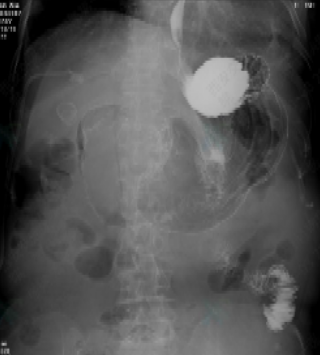

术前胃肠道泛影葡胺造影胃流出道梗阻,造影剂通过不良